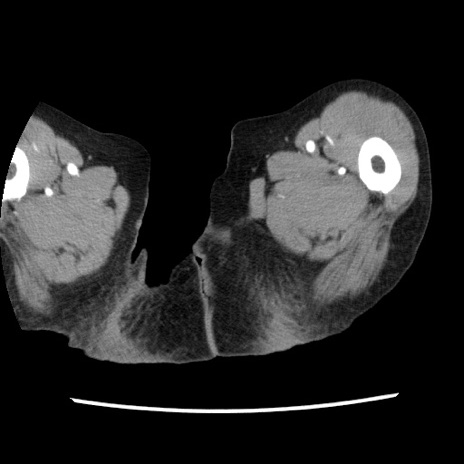

【症例】80歳代女性

【主訴】腹痛

【現病歴】8時間前から腹痛あり来院。

【既往歴】糖尿病、脂質異常症、子宮体癌にて子宮全摘術

【身体所見】意識清明・会話良好だが腹痛で苦悶様、全腹部にわたって反跳痛と圧痛あり

【データ】WBC 13600、CRP 0.14、LDH 224、CK 90